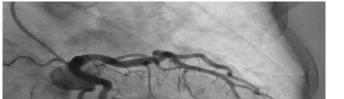

Prior to the start of the procedure, the patient must have IV access and be placed on a cardiac monitor. After informed consent has been obtained, the patient is positioned in the supine position with the head to the contralateral side of the proposed block. The physician stands at the head of the bed above the ipsilateral breast with the ultrasound screen in direct line of sight (commonly at the level of the contralateral hip). The ultrasound probe is initially placed in the sagittal plane at the midclavicular line until the clavicle, pectoralis muscles, and axillary artery and vein are visualized. The transducer is then translated caudally until the third and fourth intercostal spaces are visualized (Image 1).

At this point, the pectoralis major and minor muscles can be visualized. By rotating the transducer 45 degrees clockwise, the thoracoacromial artery can be identified between the pectoralis major and minor muscles. Also, the serratus anterior muscle should be identified resting just above the anechoic rib (Image 2).

Image 1. Initial probe placement for the pectoralis nerve block I and II illustrated on a model: the blue line indicates transducer, and the green dot indicates directional marker corresponding to ultrasound image. Image 2. Final probe placement prior to the pectoralis nerve block I and II: blue line indicates transducer, and green dot indicates directional marker corresponding to ultrasound image.